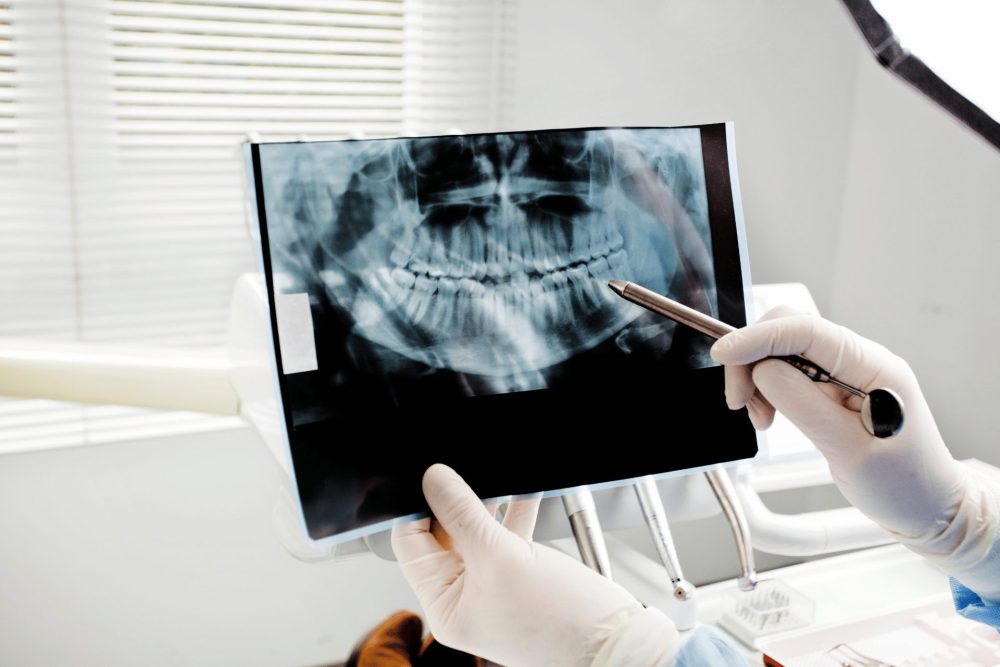

半年~1年に一度はレントゲンで状態を確認し、変化がないかを見守っていきましょう。

定期検診でレントゲンを撮り、状態を確認しておくと安心です。

まずは、歯科医院でレントゲンを撮り、自分の親知らずの状態を確認してみましょう。